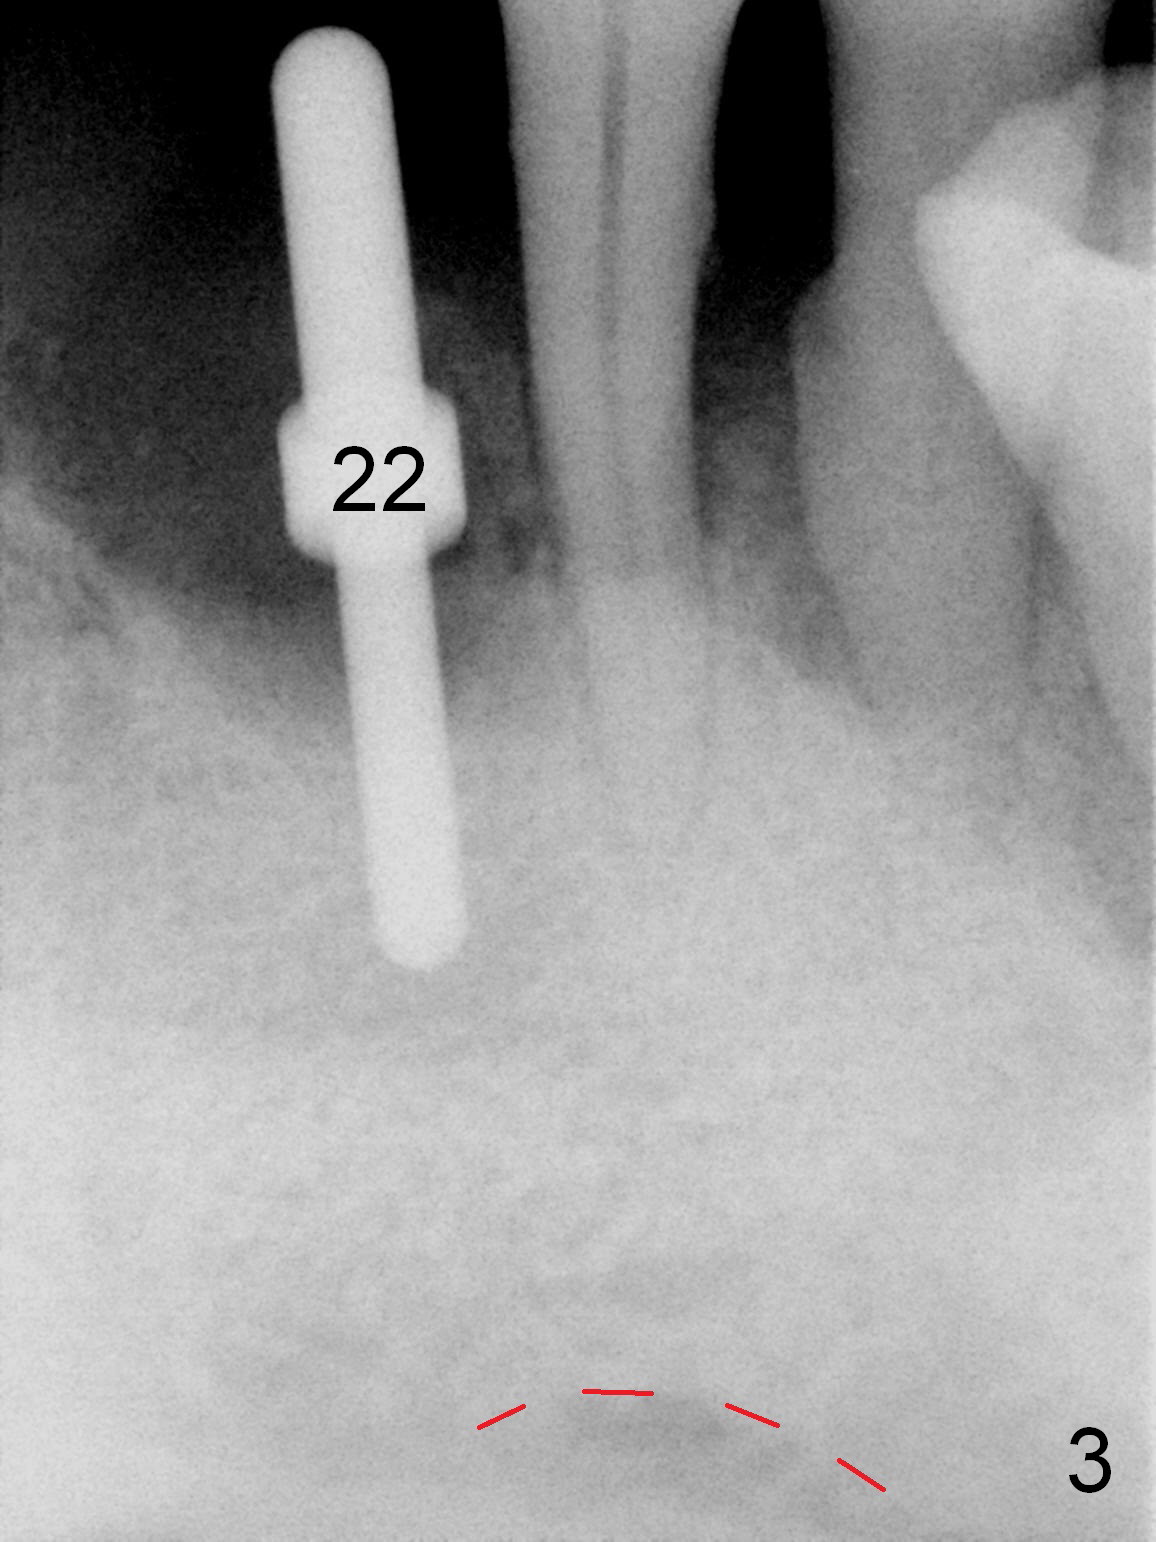

As expected, the bone density in the mandibular anterior region is found to be high during initial osteotomy (Fig.1-3).  Five implants are placed at the sites between #22 and 28 (Fig.4,5): 3x14(2) mm 1-piece (bone-level) implants in the incisor region; 4.5x17 mm 2-piece (tissue-level) ones in the canine/premolar area.  All of the implants are placed as lingual as possible.  Bone graft is placed (*).  Red dashed line: the superior border of the Inferior Alveolar Canal.  Immediate splinted provisional bridge is fabricated.  One week postop, periodontal dressing remains attached to the provisional and the gingiva.